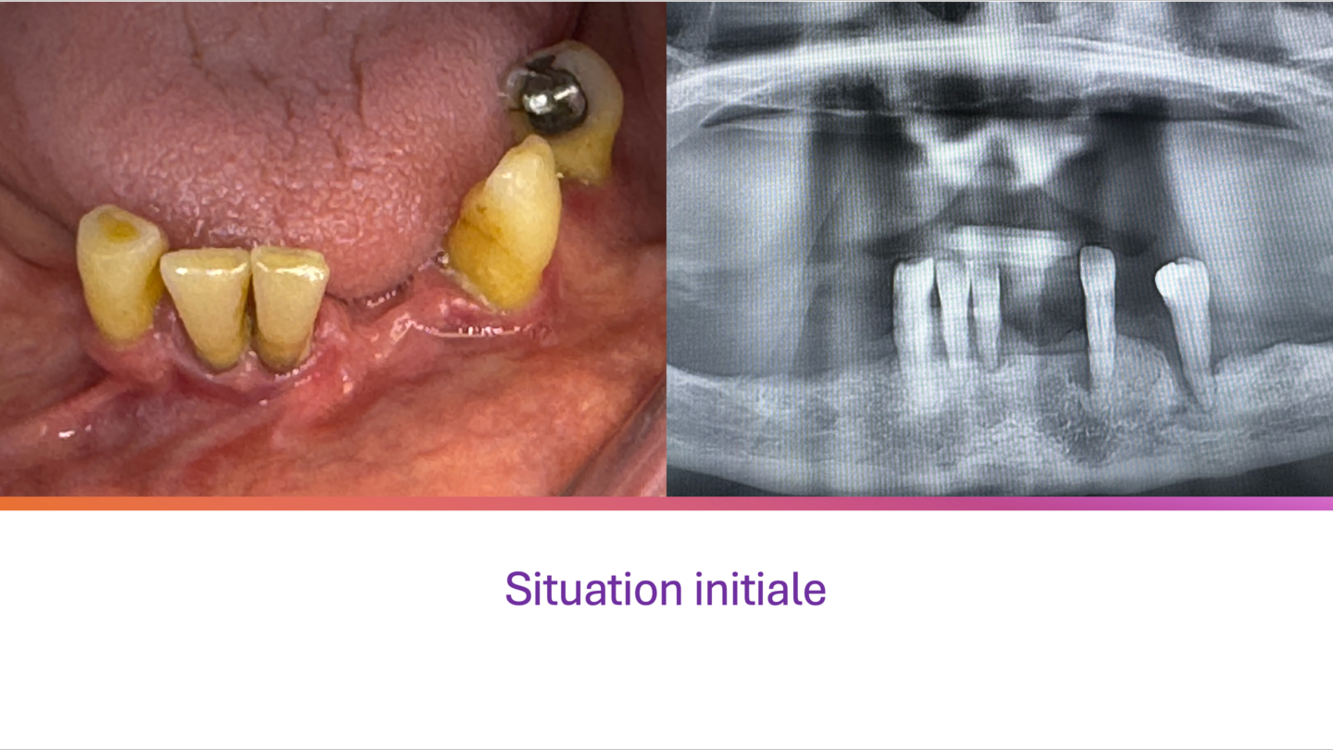

Patiente de 73 ans.

Ses dents du bas sont mobiles et douloureuses. Elles ne peuvent plus stabiliser l’ancienne prothèse du bas. La patiente vient nous voir dans l’attente d’une solution stable et esthétique.

La pose de 3 implants et les extractions sont réalisées dans la même séance; une prothèse transitoire stabilisée par 2 clips transitoires est mise en place le même jour.